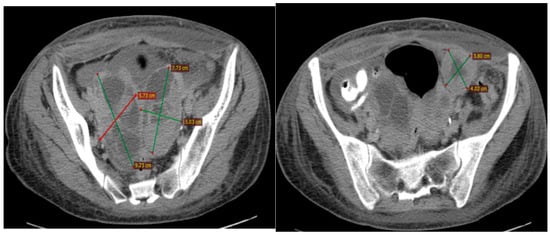

2.2.3. Examinations and Investigations

2.2.4. Diagnosis